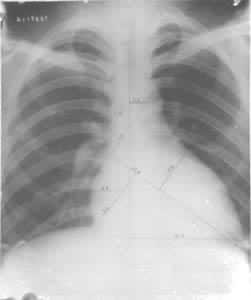

运动员尸检材料发现运动训练可引起明显的心肌肥厚。放射线检查可见运动员心脏面积和容积增大。心面积增大者以耐力训练项目运动员为最多(图1)。心面积增大的程度,多数不超过其预测面积的30%。运动员心脏容积一般也较大,中国正常成人心脏容积最大为870.68ml,中国运动员心脏容积最大者为1209.45ml,其心脏面积也最大(为+55.32%)。外国文献报道,职业自行车运动员和水球运动员心脏容积最大可达1700ml。训练内容不同对心脏的影响也有差别,耐力训练运动员的心脏以心腔扩张为主,力量练习运动员的心肌肥厚可稍占优势。

运动员心脏的X射线影像 男性,24岁,公路自行车运动员,心面积增大50%。